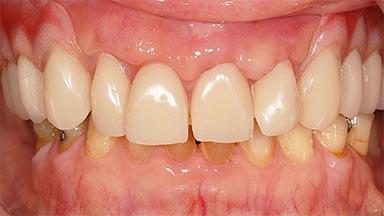

Maxillary Implant-supported Full-arch Removable Dental Prostheses for a Geriatric Patient: Sequencing the Treatment for an Optimal Outcome

A 90-year-old, essentially healthy woman requested assistance following what she determined was the loss of a dental restoration from a maxillary anterior tooth. She also complained of pain associated with tooth 11. The patient was assessed as relatively fit and healthy. She took medications for mild hypertension and to prevent angina attacks (atenolol and diltiazem). She had a form of arthritic joint degeneration affecting several joints; especially in her hands and fingers. When required she used an NSAID (meloxicam) for pain management. She reported living alone in a care facility that allows for independent living, with domestic support when and if necessary and primary medical triage when required.